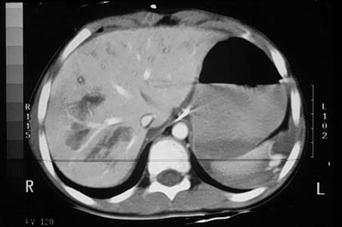

Leziune hepatica intraparenchimatoasa Leziune de lob drept

hepatic